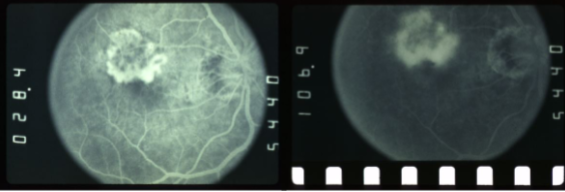

classic CNV/Gass type 2

CNVM

well defined hyperfluorescence

cartwheel or sea fan appearance

thought to break through RPE & staying sub-retinal

type 1 MNV

fibrovascular PED

late leakage from undetermined source (poorly defined neovascularization)

speckled hyperfluorescence

dye pooling late in study

poorly defined

type 2 MNV

MNV is now b/t neurosensory retina & RPE making the IVFA more obvious & well defined

IVFA shows lacy, well-group area of neovascularization

hyperfluorescent early in study

late leakage

lacy early fill of the MNV during the choroidal & arterial filling phase

may have hypofluorescence corresponding to RPE hyperpigmentation & blood in the outline of the MNV

progressive hyperfluorescence throughout the FA w/o leakage of the margins of the MNV

classic CNV

classic & occult CNV